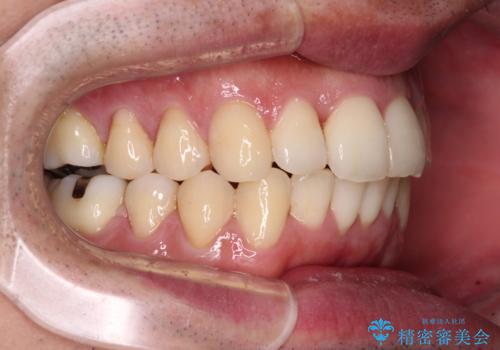

インビザラインは1日22時間を目標にマウスピースを装着することで歯列を改善するものです。

そのため、上下の歯が接触することはほとんどなく、マウスピースを介した咬合において歯列矯正が進んでいきます。

この方は元々骨格的な偏位が大きかったためか、治療中に下顎骨が上顎骨よりも右外側に誘導されて、右側の奥歯が全く咬合しない状態が続いてしまいました。

最終的にはゴムかけなどを活用して改善することができましたが、4年近い治療期間を要することとなりました。